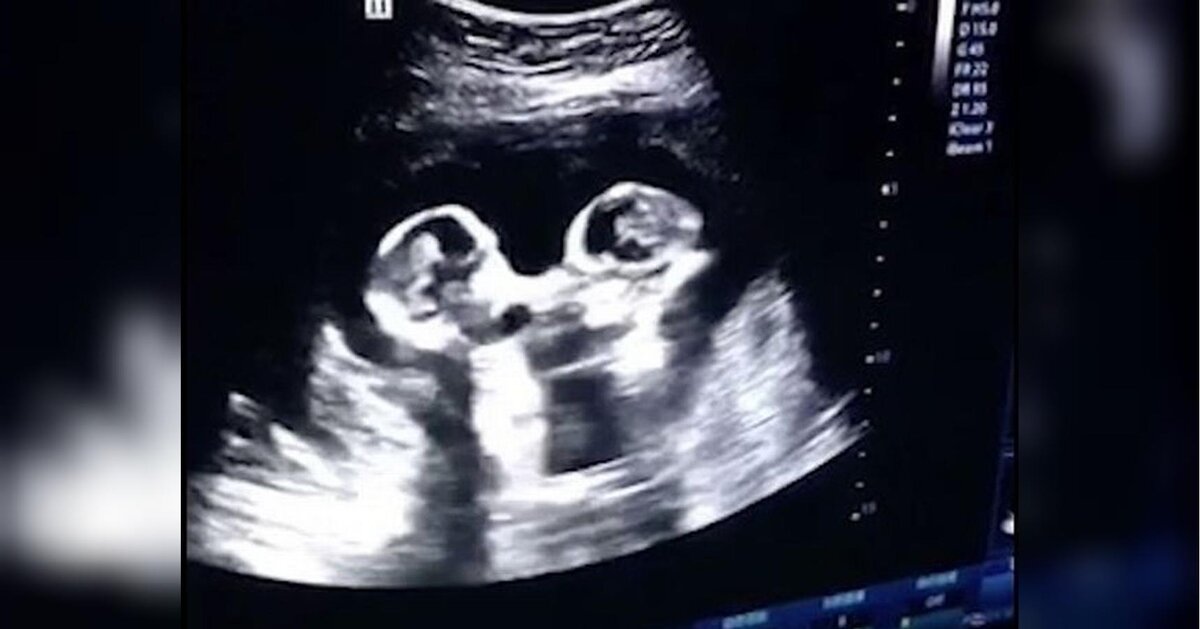

Итак, в одном из роддомов китайского городка Иньчуань произошёл необычный случай. Будущая роженица, которая ждала двойню, пришла сделать ультразвуковое обследование. Когда врач проводил обычное, даже рядовое в наше время обследование, то увиденное на мониторе повергло его в изумление. Позвав других врачей, все вместе они отчётливо видели драку ещё не родившихся девочек.

Снимки УЗИ.

На видео сёстры, поочерёдно махая кулачками, ударяли друг друга. Такая ситуация была несколько необычной. Даже, можно сказать, уникальной. И родители немного встревожились таким поведением своих будущих деток. Но врачи их успокоили, объяснив, что такие движения сестричек являются не сознательными, а рефлекторными, и потому их здоровье не подвергается никакой опасности.